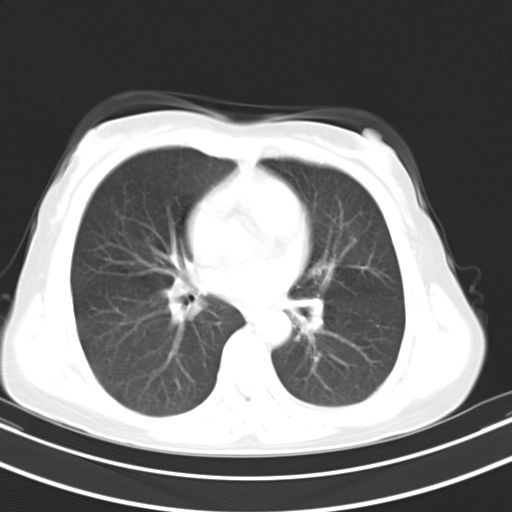

女,47岁,咳嗽胸痛一个星期,我们考虑肺结核,左下肺病灶肿瘤像不像,请高手指点。急。

考虑两肺炎症,建议治疗后复查。

考虑两肺炎症,建议治疗后复查,左侧少量胸腔积液

1)右肺上叶前段及左肺上叶舌段感染性病变;建议抗炎治疗后复查。2)左侧少量胸腔积液。